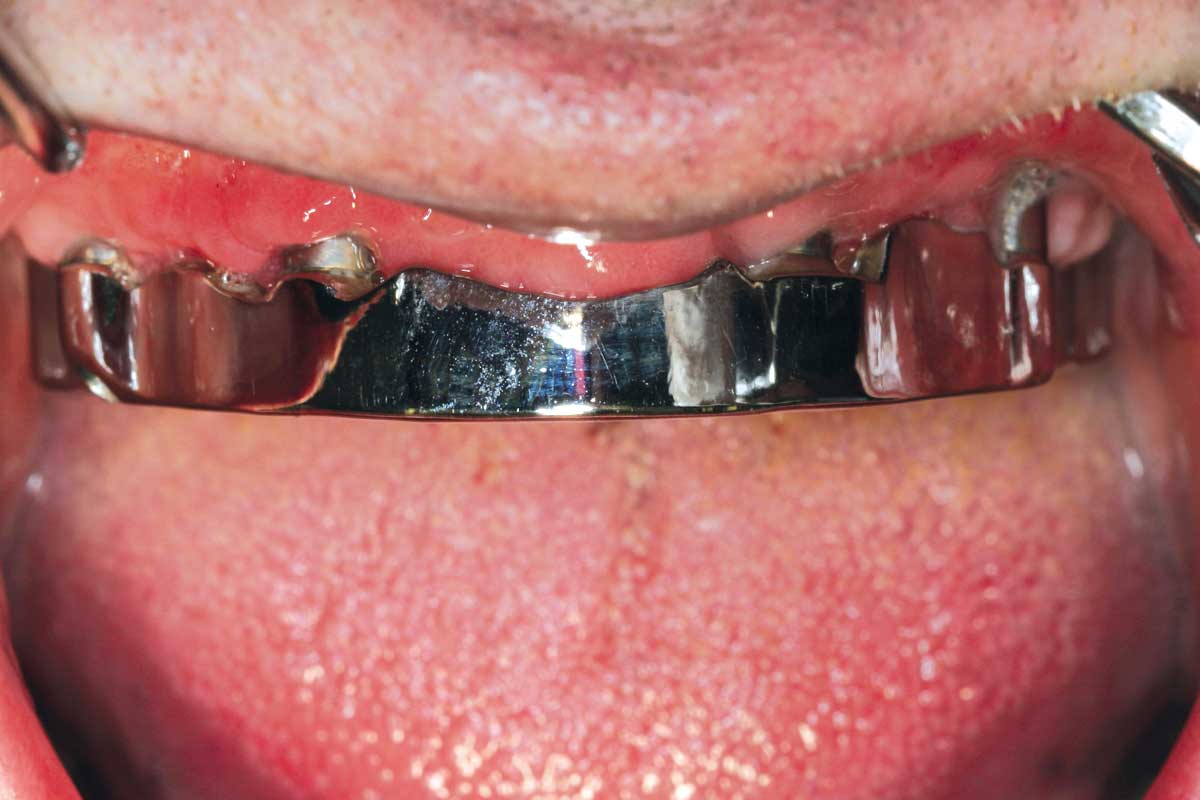

Preoperative situation – Maxillary defect in area 14-16 (loss of implant 16 due to periimplantitis, tooth 14 extracted recently and area 15 already edentulous for a while)

Bone defect in area 11-21 due to two lost implants (periimplantitis) after 15 years of function